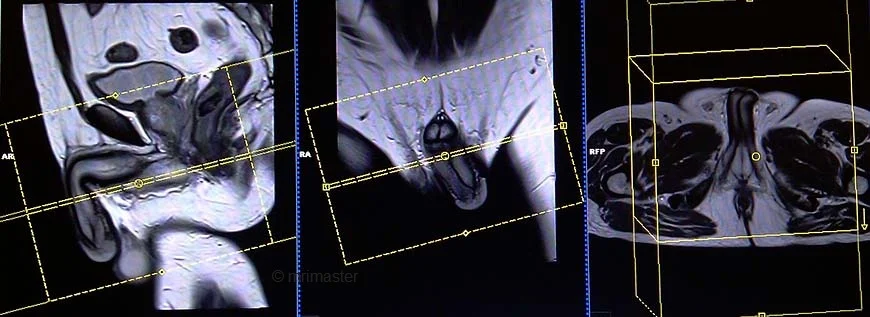

Penile mri localiser

A three-plane HASTE localizer must be taken initially to localize and plan the sequences. These are fast single-shot localizers with under 25s acquisition time, which are excellent for localizing pelvic structures. Take at least 3-4 slices in all planes to get the best results.

T2 tse sagittal 3mm SFOV

Plan the sagittal slices on the axial plane. Angle the positioning block parallel to the interpubic fibrocartilage and the anal canal (i.e. parallel to the penile base). Check the positioning block in the other two planes. An appropriate angle must be given in the coronal plane (parallel to the penis). Slices must be sufficient to cover the entire penis. The FOV must be big enough to cover the whole penis (normally 180mm-200mm).

T2 stir axial 3mm SFOV

Plan the axial slices on the sagittal plane and angle the positioning block parallel to the penile base (i.e., perpendicular to the penile shaft and glans penis). Check the positioning block in the other two planes, ensuring an appropriate angle is given in the coronal plane (perpendicular to the penile shaft and glans penis). The slices must be sufficient to cover the entire penis from the prostate down to 1cm below the glans penis.

T1 tse axial 3mm SFOV

T2 stir coronal 3mm SFOV

Plan the coronal slices on the sagittal plane and angle the positioning block parallel to the penile shaft and glans penis. Check the positioning block in the other two planes. An appropriate angle must be given in the axial plane (perpendicular to the base of the penis). The slices must be sufficient to cover the entire penis from anterior to posterior.